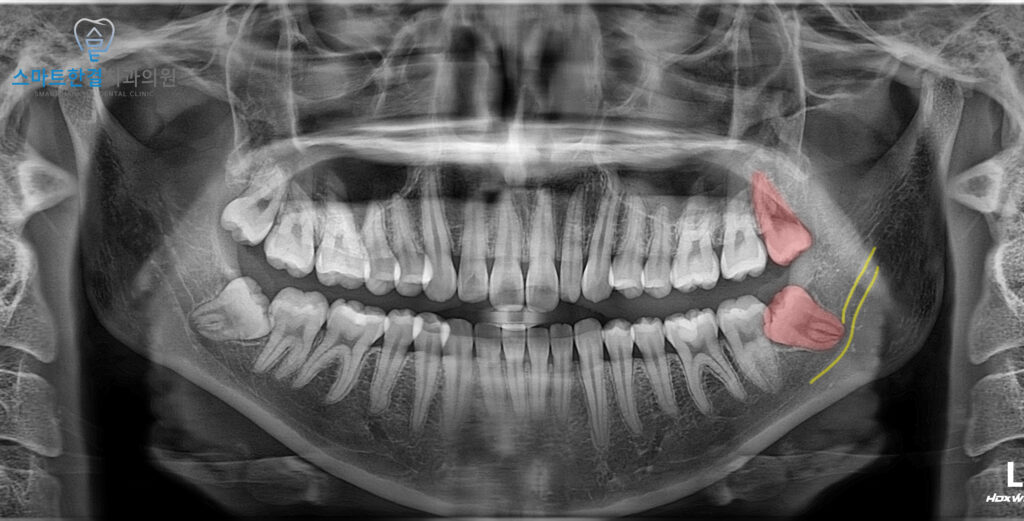

파노라마 사진에서는

왼쪽 아래 사랑니가 잇몸 안에 묻혀 있으면서

앞 치아 쪽으로 비스듬히 누워 있는

모습이 확인되었어요.

또한 육안으로 살펴보았을 때

잇몸이 약간 부어 있는 상태였어요.

잇몸 부기의 원인이 사랑니일 가능성이 높고,

비스듬히 누운 사랑니가 앞 치아에 영향을 미칠 우려가 커

왼쪽 아래 사랑니를 발치하는 동시에

위쪽 사랑니도 함께 발치하기로 결정하였답니다.